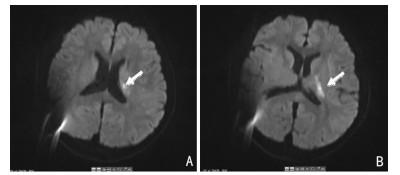

后完善颅脑MR增强+DWI证实左侧基底节区﹣侧脑室体旁新近梗死灶(图 1),同时还显示弥漫性硬脑膜增厚、明显强化,静脉窦扩张稍明显,脑下沉等低颅压影像特征。后行腰椎穿刺发现脑脊液压力15 mm水柱。24小时动态心电图、经食道心超等检查未见心源性栓塞证据。血管评估如主动脉弓及三分叉彩超、颈部CTA、头颅MRA未发现颅内、外大动脉狭窄及动脉夹层等。类风关抗体谱、磷脂综合征抗体、抗核抗体谱、血管炎系列均未见明显异常。颅脑MRV提示颅内静脉未见明显异常。

| A、B:提示左侧基底节区-侧脑室体旁新近梗死灶(箭头所示)。 图 1 头颅磁共振DWI序列 |